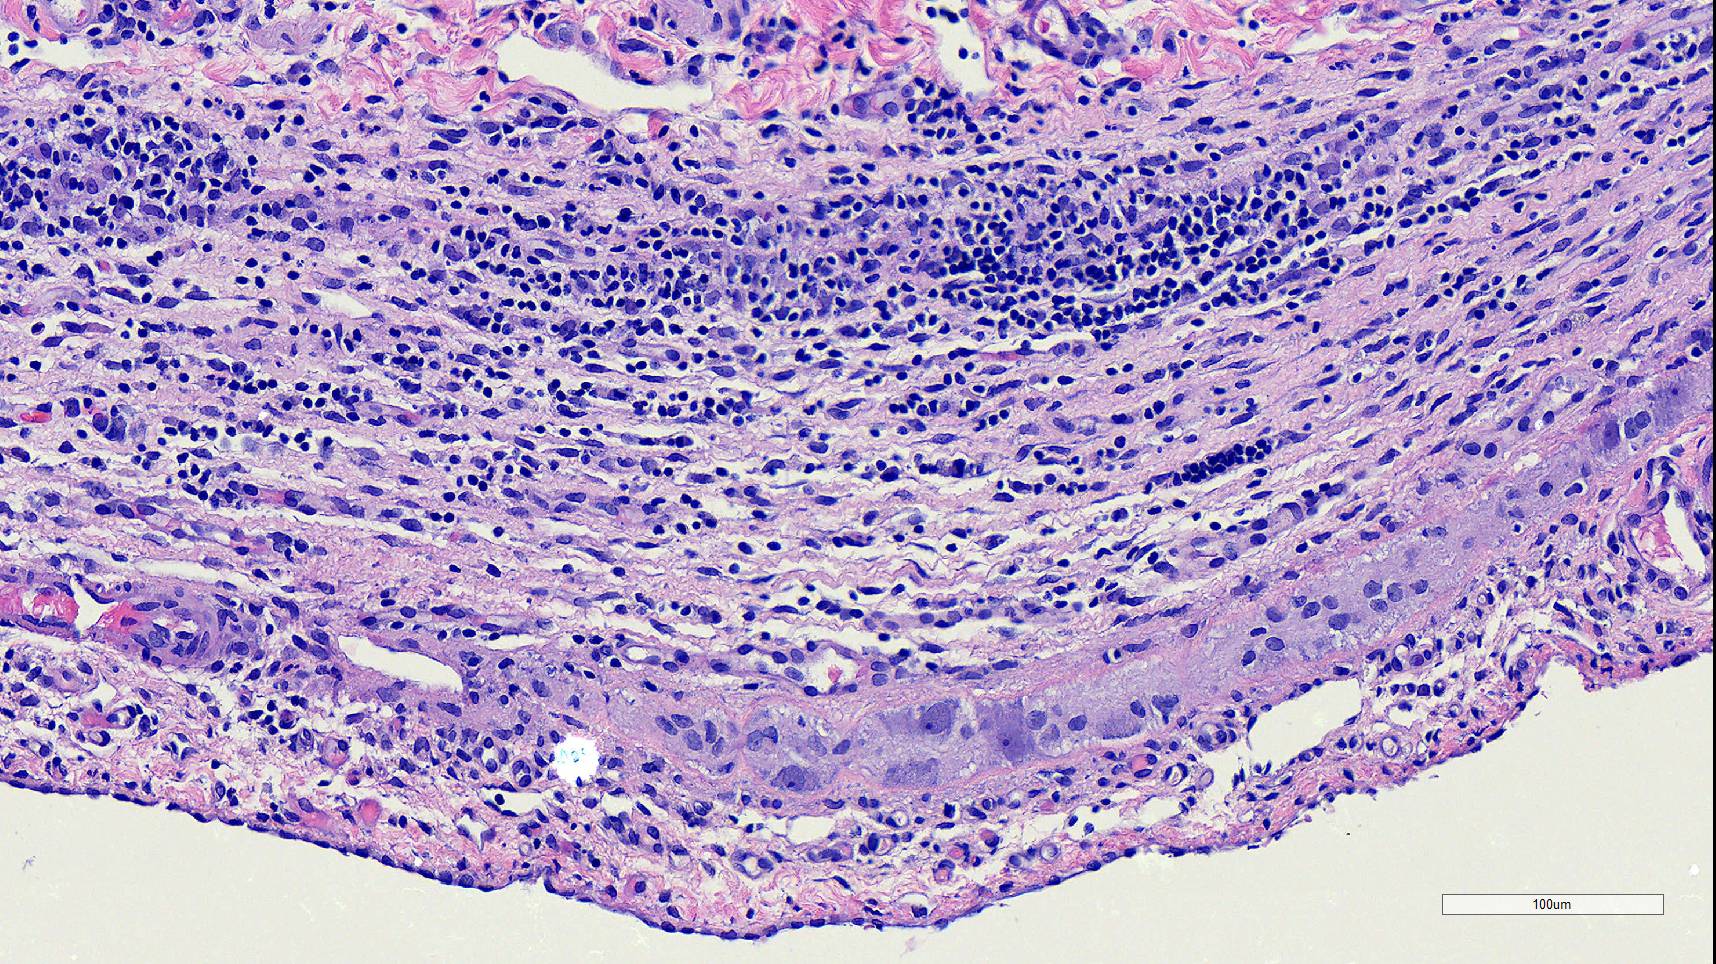

Microscopic Description:

Duodenum, jejunum and ileum: Diffusely throughout the sections, there is partial to complete loss of the leiomyocytes of the outer and inner muscularis, which are multifocally replaced by loose fibrous connective tissue (fibrosis). The remaining smooth muscle is infiltrated by large numbers small and intermediate lymphocytes, few macrophages and neutrophils. The same inflammatory infiltrate is present throughout the muscularis mucosae. Remaining leiomyocytes have pale, frequently vacuolated cytoplasm. In the submucosa, muscularis and serosa there are small to moderate numbers of perivascular lymphocytes. Small lymphocytes, and infrequently neutrophils, surround or infiltrate the myenteric and submucosal ganglia, though neurons do not exhibit degenerative changes. The lamina propria contains a markedly increased number of lymphocytes, plasma cells and a mildly increased number of eosinophils. The epithelium is diffusely overlain by myriad bacterial rods. The serosa is mildly expanded by increased clear space (edema) and is lined multifocally by markedly hypertophied mesothelium. In the stomach a similar process is observed but restricted to the outer aspect of the muscularis with a patchy/multifocal distribution and sparing of the muscularis mucosae. (section not submitted).

Microscopic findings reported for this condition consist of mild to marked mononuclear infiltrate, myofiber degeneration and fibroplasia or fibrosis centered within the muscularis propria of the stomach, small and large intestinal wall with the jejunum being the most severely and chronically affected segment.7,15 In early lesions the inflammation and smooth muscle degeneration are segmental, random between the outer and inner muscularis layers and sparing of the muscularis mucosae.15 Concurrent cecal involvement leading to impaction has also been described.5 Consistent histologic findings included T-lymphocyte inflammation within the muscularis propria with relative sparing of the mucosa, submucosa and neural plexuses.14 In one case report the inflammatory infiltrate was predominantly of B-lymphocytes and featured extensive angiogenesis.6 Leiomyocytes appear to be the target of the inflammation given the presence of various stages of degeneration leading to complete myofiber loss in chronic stages of the disease. Superficial inflammation is a frequent secondary finding in CIPO and has been associated with bacterial overgrowth, which were changes observed in this case.6 Neuropathy has not been a feature in most reports of canine CIPO. Inflammatory cells obscuring the myenteric and submucosal plexuses in this case were considered an extension from the neighboring inflammation as no degenerative changes were observed in the neurons. Myenteric ganglionitis has, however, been reported occurring concurrently with leiomyositis.10

Small intestine: Leiomyositis, lymphocytic, chronic, diffuse, severe, with marked smooth muscle loss and fibrosis.